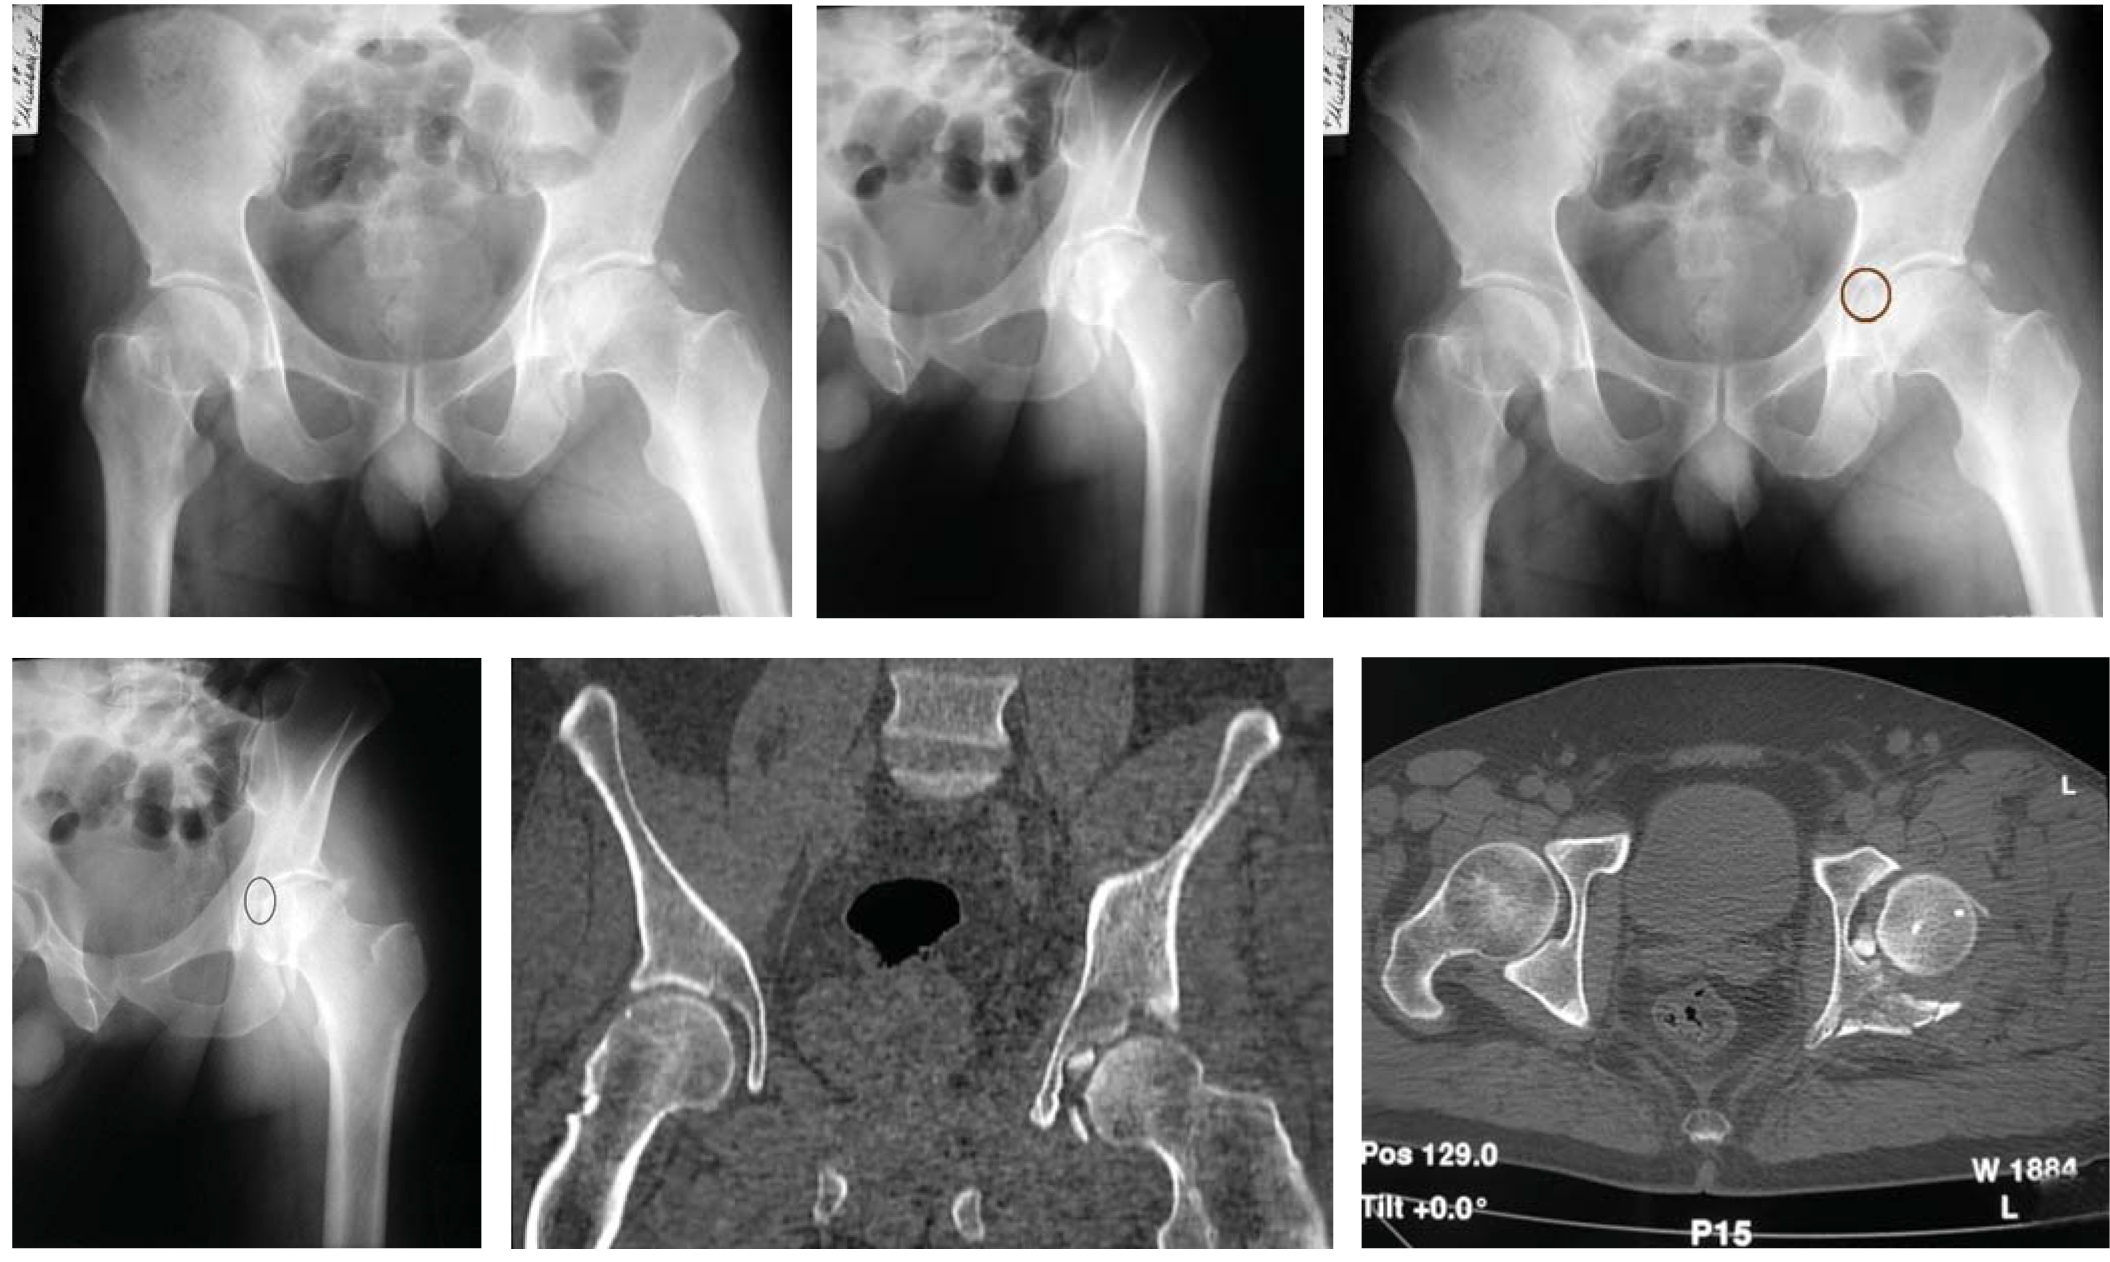

Наблюдение №3

На обзорной рентгенограмме в следующем клиническом примере определяем целостность подвздошно-седалищной линии (рис. 3, а). Сохранение целостности этой структуры позволяет исключить переломы, при которых плоскость излома проходит через заднюю колонну. К этим переломам относят: перелом задней колонны, поперечный перелом, перелом задней колонны, ассоциированный с переломом задней стенки, поперечный перелом, ассоциированный с переломом задней стенки, Т-образный перелом, перелом передней колонны, ассоциированный с задним полупоперечным, двухколонный перелом (рис. 3, б).

Рис. 3.а — обзорная рентгенография таза при поступлении; б — первый этап определения атипичного внесуставного перелома передней колонны; в — второй этап определения атипичного внесуставного перелома передней колонны; г, д, е, ж — верификация внесуставного перелома передней колонны с помощью прицельных рентгенограмм в косой-подвздошной и косой-запирательной проекциях и компьютерной томографии.

Рис. 4.а, б — перелом вертлужной впадины слева; Ц — оскольчатый характер перелома задней стенки вертлужной впадины.

Сочетание повреждения подвздошно-гребешковой линии и контуров запирательного отверстия позволяет исключить перелом задней стенки, т.к. при подобных переломах сохраняется целостность обеих линий. Так же возможно исключить перелом передней стенки, при котором имеет место повреждение только подвздошно-гребешковой линии без повреждения контуров запирательного отверстия (рис. 3, в). Таким образом, методом исключения диагностирован перелом передней колонны.

Однако при наличии признаков перелома передней колонны, отсутствует повреждение суставной поверхности, что возможно подтвердить с помощью поли проекционной рентгенографии и компьютерной томографии. При анализе прицельных снимков видно, что линии перелома не проходят через суставную поверхность, что так же подтверждается на трехмерной компьютерной реконструкции костей таза (рис. 3, в—ж).

Исходя из результатов трехмерной реконструкции, наиболее подходящим диагноз можно сформулировать, используя классификации Л.Г. Школьникова (1966) или А.Ф. Лазарева (1992) [3, 4]. Согласно первой классификации этот перелом соответствует типу 3.В.б), т.е. перелом с нарушением непрерывности тазового кольца, как в переднем, так и заднем отделах.

Согласно второй классификации этот перелом относится к полифокальным повреждениям таза с вовлечением передних и задних отделов.

Наличие нескольких линий перелома не всегда свидетельствует об ассоциированном характере перелома (по классификации Judet—Letournel). Локализация этих линий может быть в пределах одной плоскости, что свидетельствует об оскольчатом характере перелома. На рентгенограммах (рис. 4, а, б) представлен пример оскольчатого перелома задней стенки вертлужной впадины.

При видимом наличии нескольких линий перелома, отмечается целостность других референтных линий, что свидетельствует о локализации очага повреждения только задней стенки (рис. 4, в, г).